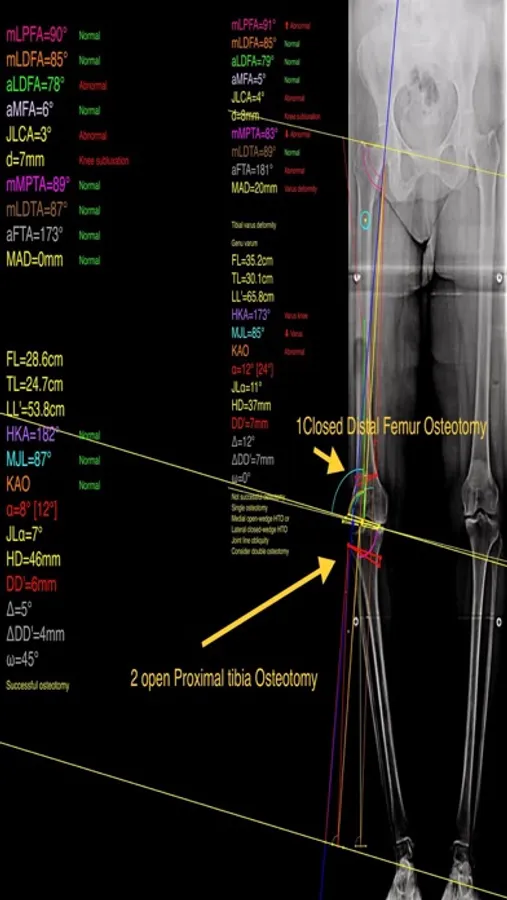

The app assists at preoperative correction planning by calculating :

-the amount of correction preoperatively by calculating the dimension of wedge size , the correction angle and osteotomy gap opening or closing.

-mechanical axis deviation (in mm) MAD, anatomical and mechanical femoral axes angle (aMFA),mechanical lateral proximal femoral angle (mLPFA), mechanical lateral distal femoral angle(mLDFA), joint line convergence angle (JLCA),mechanical medial proximal tibial angle (mMPTA), Mechanical lateral distal tibial angle (mLDTA), Hip Knee Ankle line (HKA) ,Mid joint line (MJL) orientation.

-objectively the deviation or deformity in the frontal plane (varus or valgus) and differentiate the level of deformity (femoral and or tibial origin) and according to measured angles objectively suggest where indicated, medial or lateral, open or closed-wedge distal femur osteotomy or high-tibial osteotomy or double osteotomies and avoiding unwanted obliquity of the joint line

-change the planned mechanical axis to pass at the preferred percentage (Fujisawa point) after evaluation of the residual cartilage thickness left on the involved compartment.

select the location of hinge point of correction osteotomy for planning of varus or valgus corrections

-evaluate in real time the success of intended osteotomy by evaluating the kinematic alignment of the knee (KAO), avoiding residual joint obliquity or malalignment.

-measure the correction angle adjusted due to ligament instability and preoperatively calculate the height of osteotomy gap opening.

-pressing + or - button, one degree of correction is added or subtracted respectively and the second plane of osteotomy emerges and printed in screen real offering real time simulation of the wedge osteotomy in an instant to comprehend in real time what parameters are affected and modify favourably the correction angle. All above mentioned angles and all limp axes are redrawn and updated accordingly for the given new correction angle. The drawn schematic gives the impression of settings act as a whole interchangable interacting unit.

-to combine correction- Biplanar-, at coronal plane and sagittal plane (based on Hernigou 2001 calculations ) on tibia slope and provide the direction of the plane (ω angle) in which the osteotomy (open or closed) should be made ,the height the opening or closing wedge and the correction angle (Δ angle),